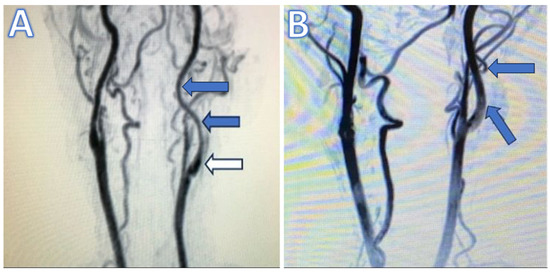

Figure 1. (A) Preoperative magnetic resonance (MR) angiography illustrating long-segment tubular stenosis. Blue arrows point to the tubular stenotic sections, while white arrow indicates the unaffected carotid bulb. (B) Postoperative MR angiography in the first month shows the dilatation of the internal carotid artery (blue arrows) compared to the preoperative MR angiography.

Patients were primarily assessed using MR and/or CT angiography. Our selection process and criteria were particularly underscored by the presence of a first segment, which is the cervical segment (according to Ziyal [14] and Bouthillier [15]) of ICA long-segment tubular stenosis observable on cervical MRI angiography, which starts from the aorta, strictly within the realm of tubular stenosis that is not eligible for endovascular treatment, thus aligning with our targeted focus and diagnostic precision, as shown in Figure 1. This segment is referred to as ‘C1’ following the classifications by Ziyal et al. [14] and Bouthillier et al. [15], which is not to be confused with the ‘C1’ segment in the Fischer classification, where ‘C1’ represents the intracranial segment from the ICA’s termination to the origin of the posterior communicating artery. Hence, the Fischer classification is not considered in our study of the cervical ICA segment (C1) [16].